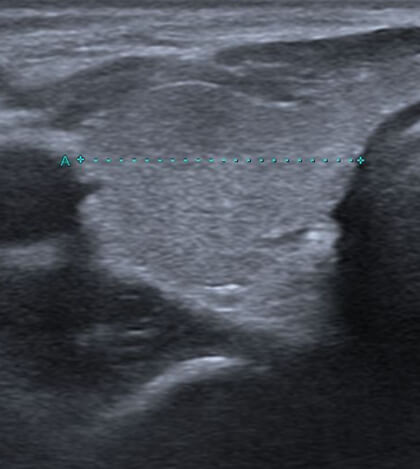

治療後

患部が黒っぽく映る「低エコー像」が特徴的です。また、触診で非常に硬いしこりのように触れることがあります(「石のように硬い」と表現されることもあります)。